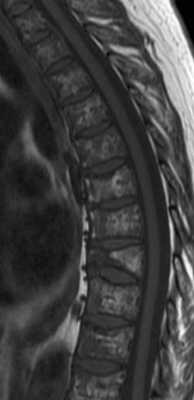

На рентгенограмма, КТ или МРТ поражение типично литическое, каплевидное, четко очерченное. При МРТ позвоночника такие очаги особенно отчетливо видны по замещению желтого костного мозга.

МРТ позвоночника. Т1-взвешенная МРТ. Множественная миелома